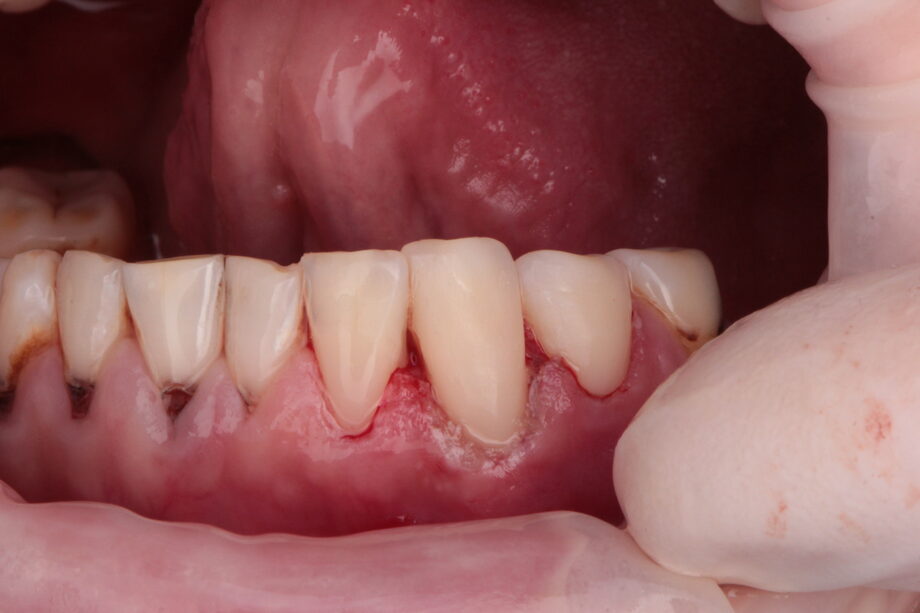

Недостаточное поступление кальция, фосфора и фтора, что негативно сказывается на состоянии зубной эмали . Особый состав слюны, содержащей малое количество микроэлементов .

На самом деле одной из функций слюны является реминерализация зубной эмали . За счет отложения соединений, составляющих зубную эмаль, постоянно происходит восстановление микродефектов зуба . Если неблагоприятные факторы превышают адаптивные возможности организма (чрезмерное потребление сладкого, мало кальция в рационе), то возникает кариес .